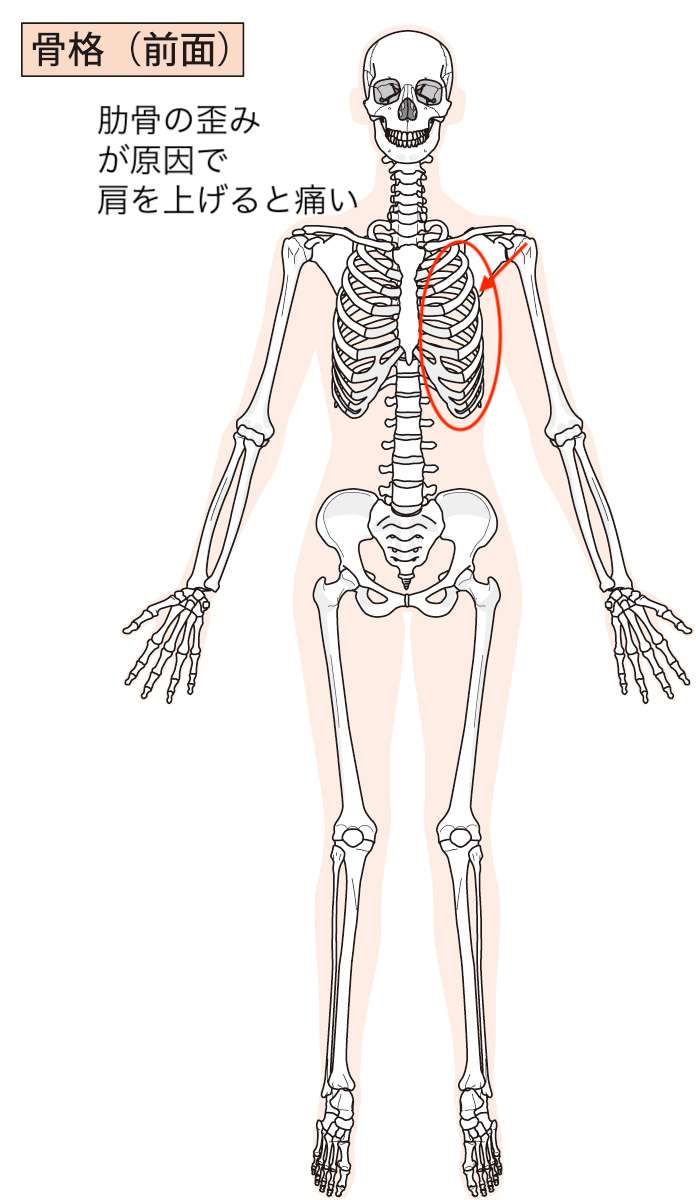

二枚目のこの図もご覧いただくとわかるかと思いますが、「肋骨」自体の歪みがあることがわかり、その影響で肩を上げるような動作で肩関節に負担がかかってしまい「肩が痛い」症状が出現することがわかりました。

「背骨」「肋骨」の歪み、両方ともに肩を痛めた際に、歪みがつくられたと考えられました。

つまり、肩関節自体に問題はなく、炎症などが起こって痛いわけではないということです。

あくまで「背骨」や「肋骨」が歪んでしまっている影響を受けて肩を動かした時、夜間寝る体勢になった時に症状を感じるという状態であるということがわかりました。